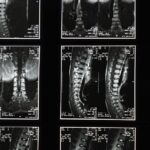

EN BREF La décompression spinale est une méthode thérapeutique non invasive visant à soulager les douleurs liées à la colonne vertébrale en réduisant la pression sur les disques intervertébraux et les nerfs environnants. Accessible à Montréal, cette technique est particulièrement…

EN BREF La décompression spinale est une technique thérapeutique non invasive qui vise à soulager les douleurs liées à la colonne vertébrale, notamment celles causées par des hernies discales ou la compression nerveuse. Accessible à Montréal, cette méthode permet une…

EN BREF La décompression vertébrale est une méthode thérapeutique non invasive visant à soulager les douleurs chroniques de la colonne vertébrale. À Montréal, ce service est particulièrement recommandé pour ceux qui souffrent de hernies discales ou de stenose spinale. En…

EN BREF En bref, la décompression neurovertébrale est une méthode non invasive qui vise à soulager les douleurs causées par les affections de la colonne vertébrale, telles que les hernies discales et la sciatique. Accessible à Montréal, ce traitement est…

EN BREF La décompression neurovertébrale est une méthode thérapeutique non invasive conçue pour soulager les douleurs liées aux troubles de la colonne vertébrale, notamment les hernies discales et les bombements discaux. Accessible à Montréal, ce service est particulièrement recommandé pour…

EN BREF Le bombement discal est une condition médicale où un disque intervertébral se déforme anormalement, entraînant une pression sur les nerfs adjacents. À Saint-Mathias-sur-Richelieu, les traitements comme la décompression neurovertébrale sont recommandés pour soulager ces douleurs. Ces méthodes non…